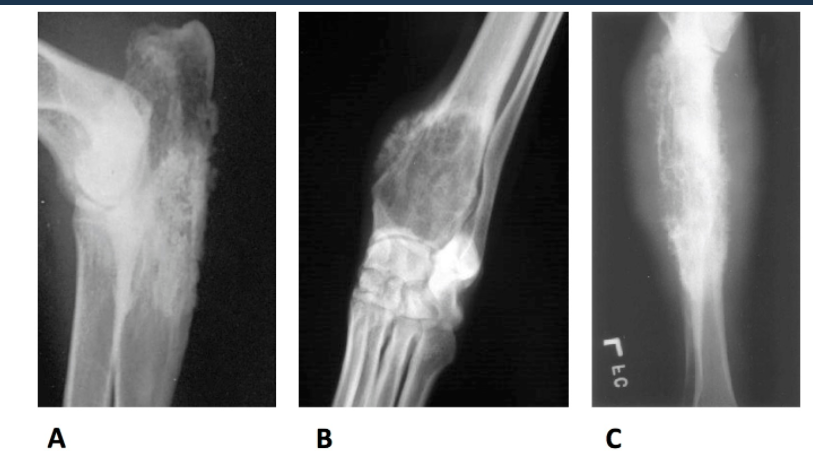

Which of the following is osteosarcoma?

a. A

b. B

c. C

d. all of these